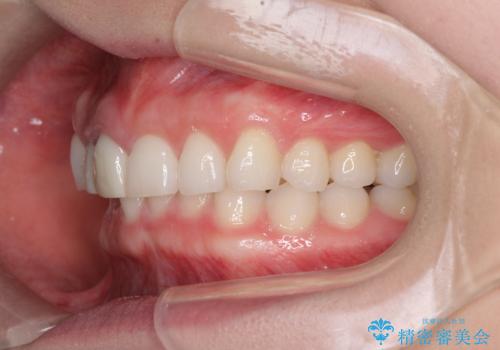

治療前、下顎前歯はほとんど見えない咬み合わせでしたが、矯正治療によりディープバイトが改善されました。

矯正治療中に前歯2本のクラウンは外れてしまい、途中仮歯に替える必要があったので期間は掛かりましたが、歯列も整い、負担のかからない咬み合わせを達成することができました。